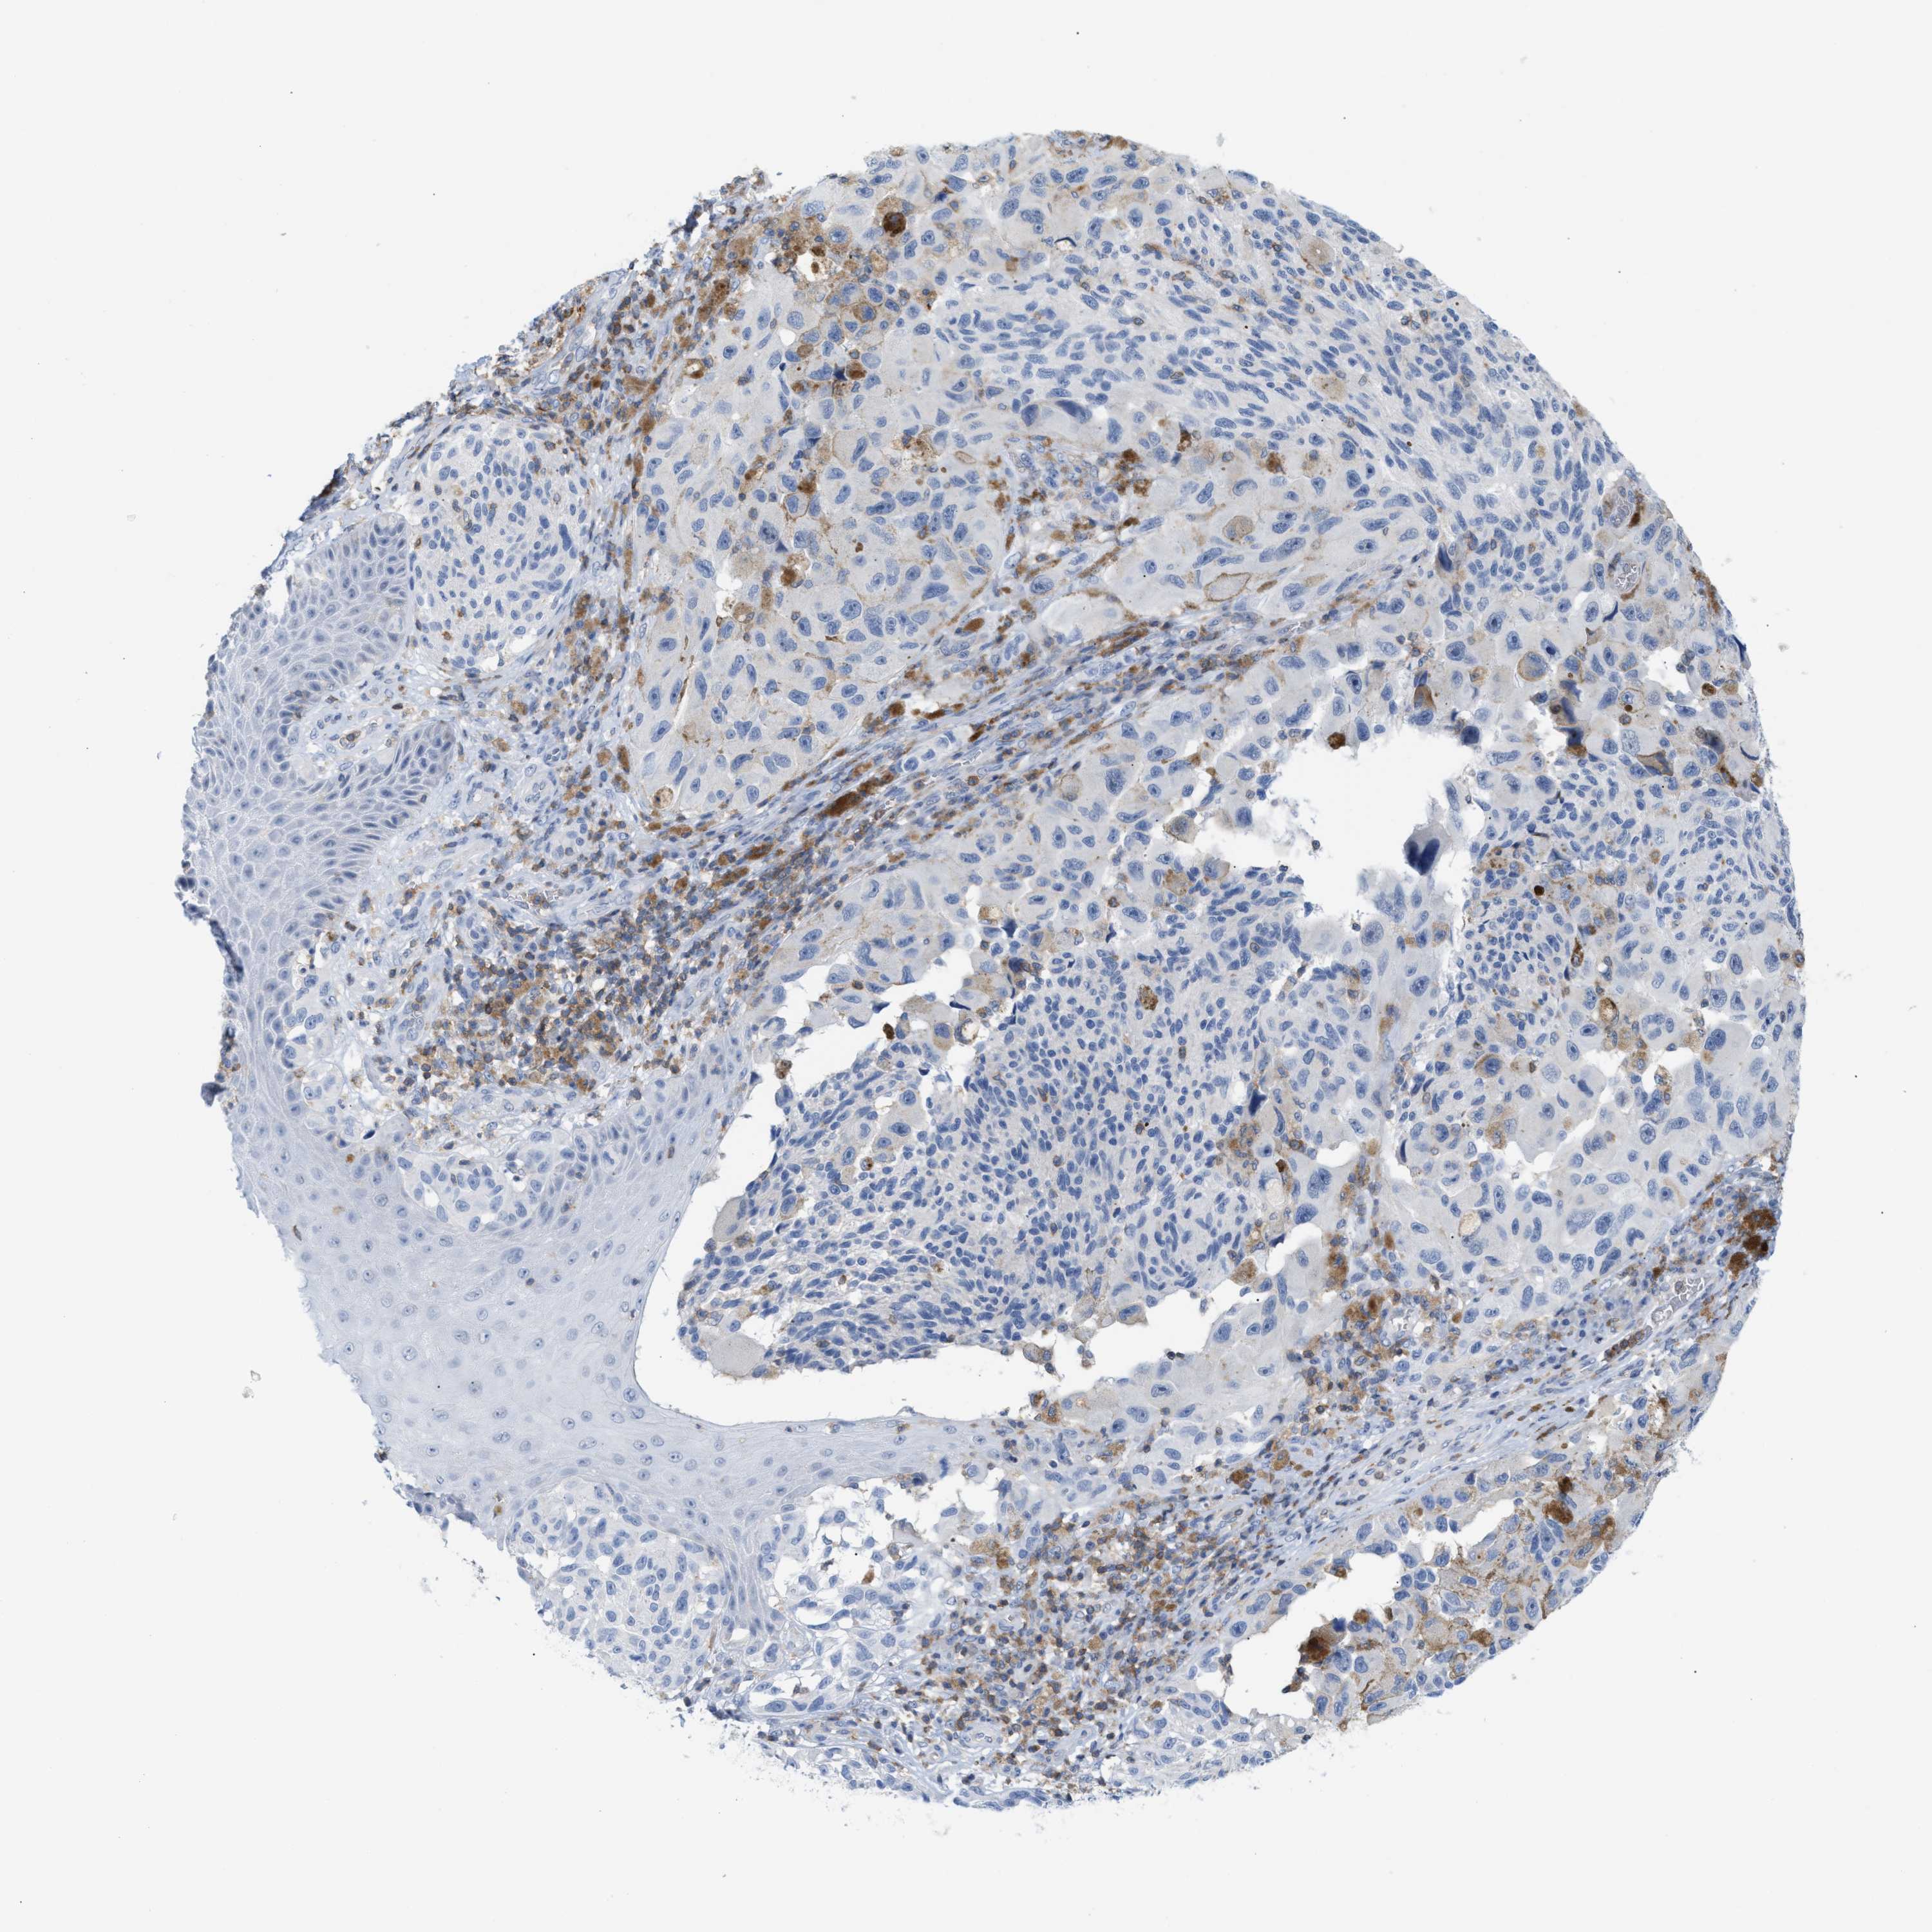

MELANOMA - Protein expressioni

A mouse-over function shows sample information and annotation data. Click on an image to view it in a full screen mode. Samples can be filtered based on level of antibody staining by selecting one or several of the following categories: high, medium, low and not detected. The assay and annotation is described here.

Note that samples used for immunohistochemistry by the Human Protein Atlas do not correspond to samples in the TCGA dataset.

Antibody stainingi

Antibody staining in the annotated cell types in the current human tissue is reported as not detected, low, medium, or high, based on conventional immunohistochemistry profiling in selected tissues. This score is based on the combination of the staining intensity and fraction of stained cells.

Each image is clickable and will lead to virtual microscopy that enables deeper exploration of all samples and also displays staining intensity scores, fraction scores and subcellular localization as well as patient and tissue information for each sample.

Antibody HPA018467

Antibody CAB005247

Staining

High

Medium

Low

Not detected

Intensity

Strong

Moderate

Weak

Negative

Quantity

>75%

75%-25%

<25%

None

Location

Nuclear

Cytoplasmic/membranous

Cytoplasmic/membranous,nuclear

Malignant melanoma, NOS

Malignant melanoma, Metastatic site